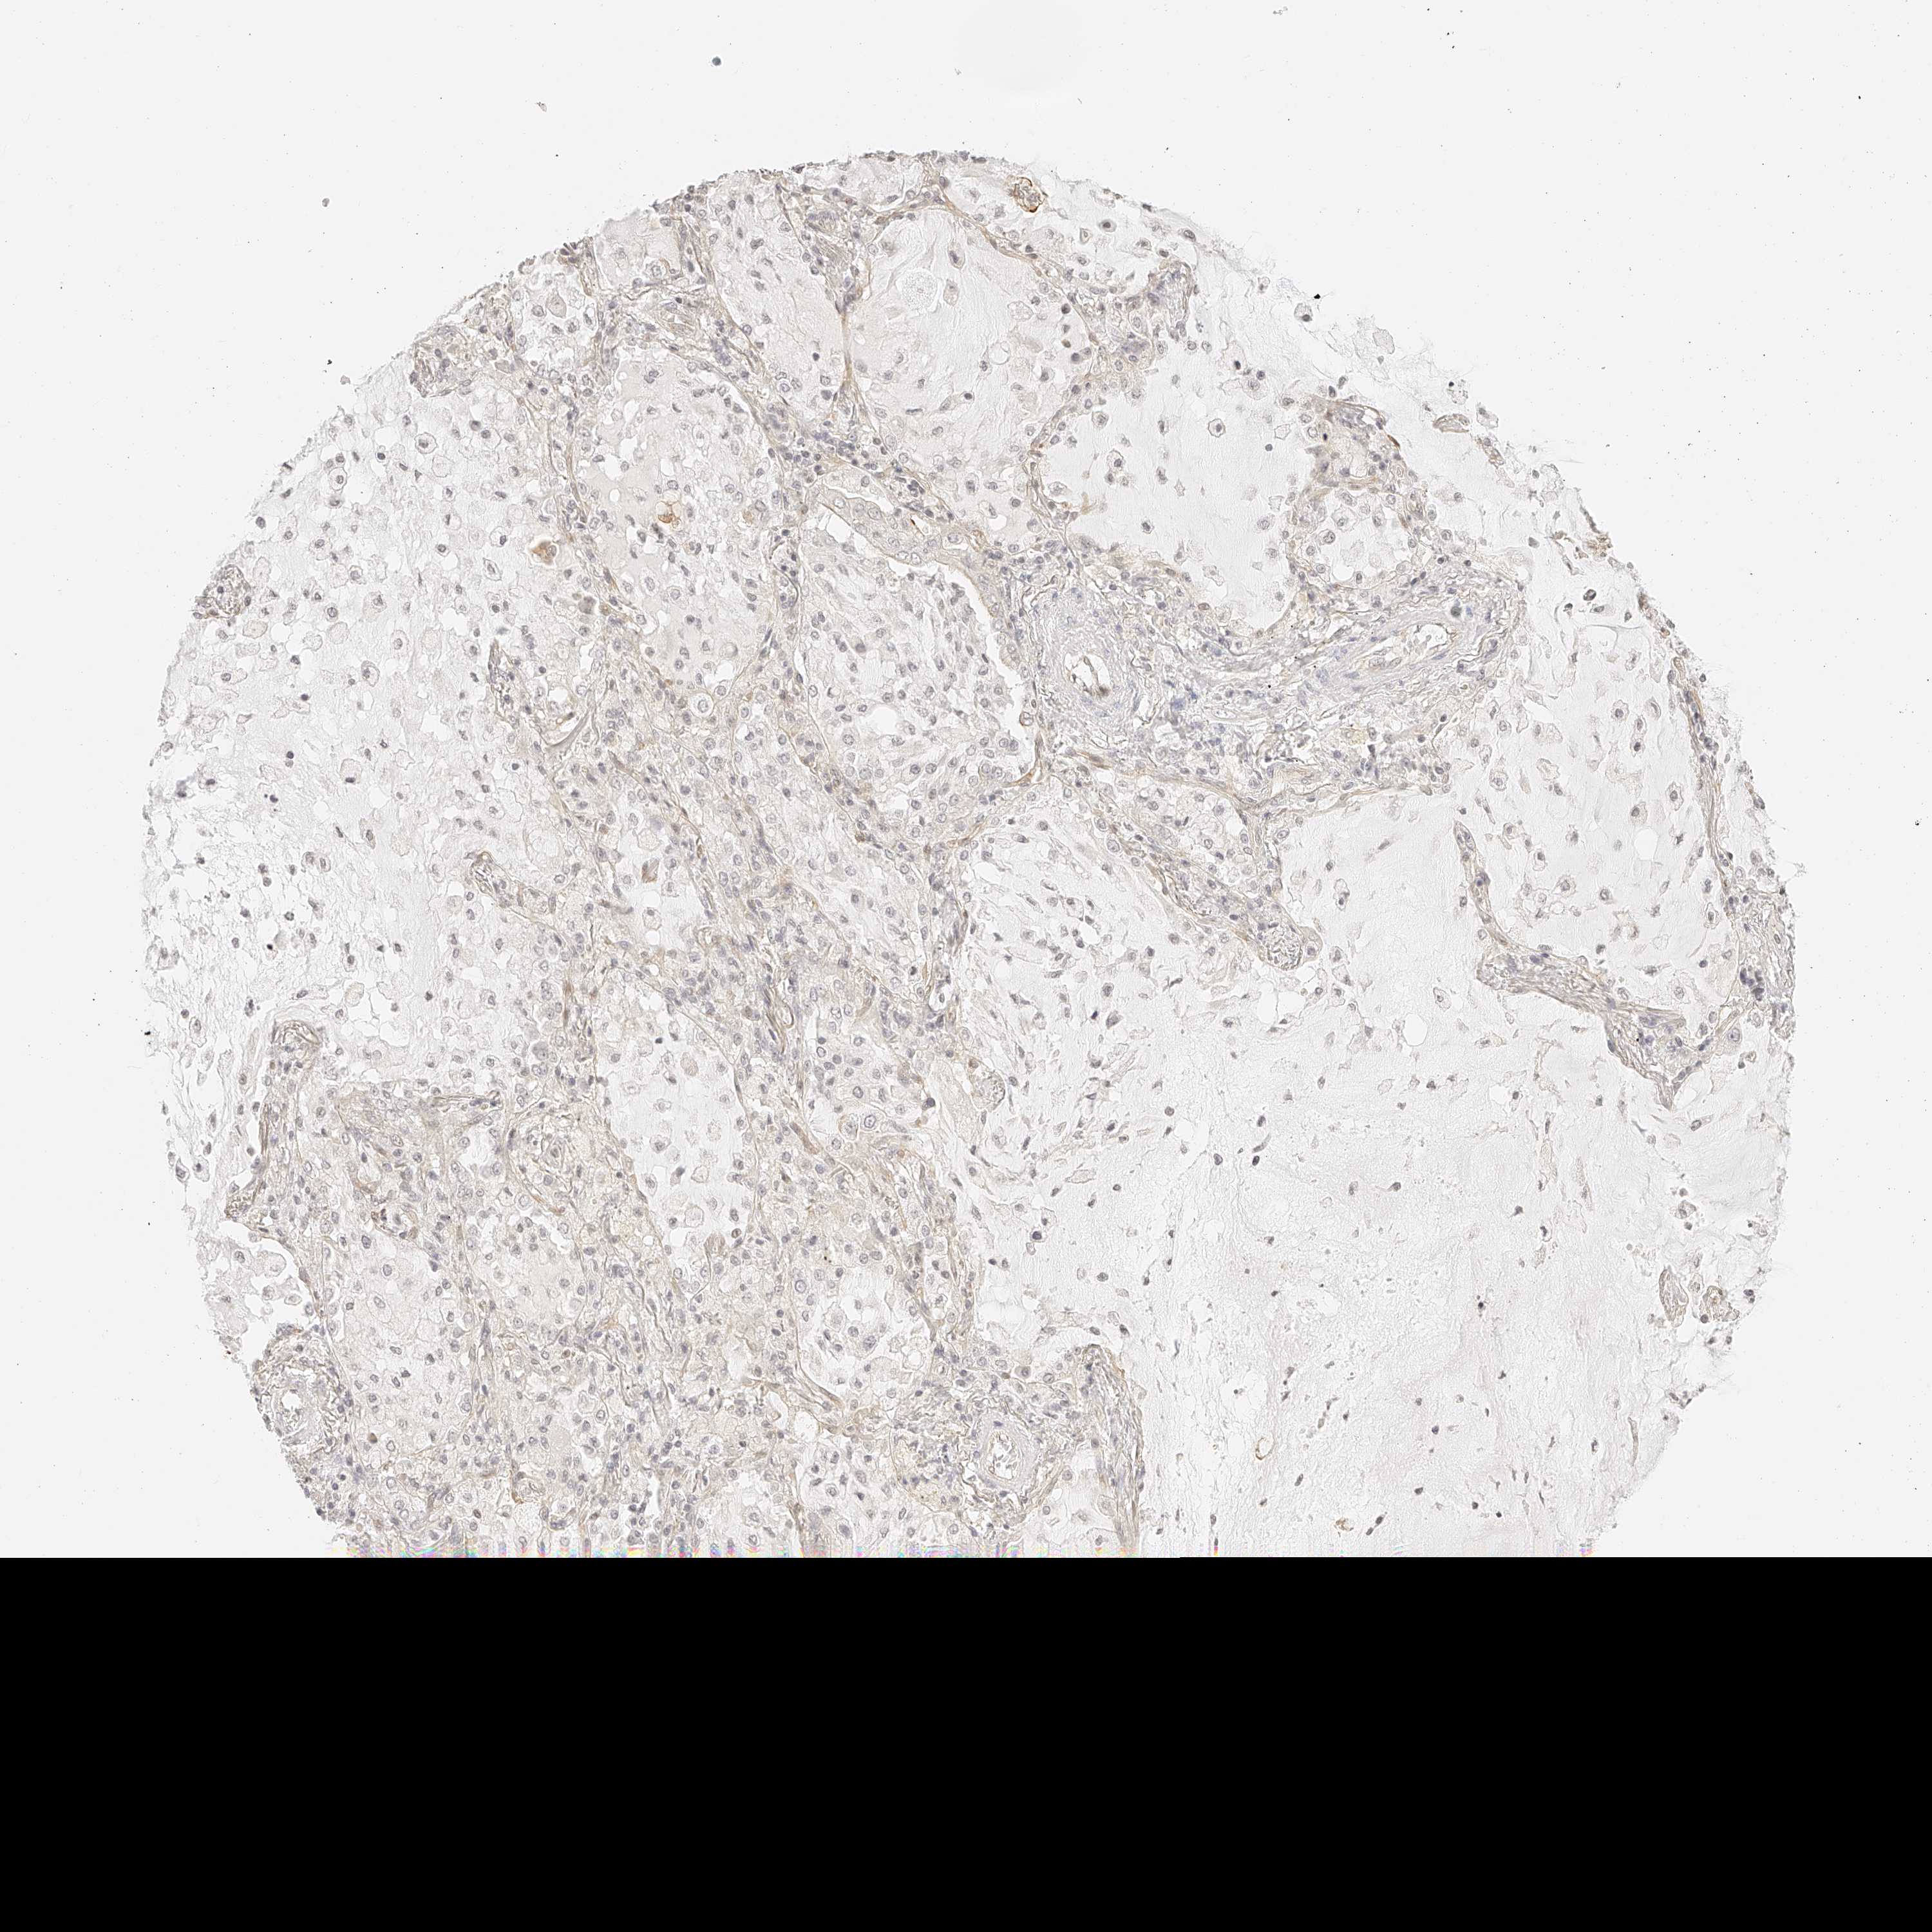

LUNG SQUAMOUS CELL CARCINOMA (TCGA) - Interactive survival scatter ploti

The Survival Scatter plot shows the clinical status (i.e. dead or alive) for all individuals in the patient cohort, based on the same data that underlies the corresponding Kaplan-Meier plots. Patients that are alive at last time for follow-up are shown in blue and patients who have died during the study are shown in red.

The x-axis shows the expression levels (FPKM) of the investigated gene in the tumor tissue at the time of diagnosis. The y-axis shows the follow-up time after diagnosis (years). Both axes are complimented with kernel density curves demonstrating the data density over the axes. The top density plot shows the expression levels (FPKM) distribution among dead (red) and alive patients (blue). The right density plot shows the data density of the survived years of dead patients with high and low expression levels respectively, stratified using the cutoff indicated by the vertical dashed line through the Survival Scatter plot. This cutoff is automatically defined based on the FPKM cutoff that minimizes the p-score. The cutoff can be changed by dragging the vertical line or by entering a cutoff value in the square labeled "Current cut-off".

Under the Survival Scatter plot the p-score landscape (black curve; left axis) is shown together with dead median separation (red curve; right axis). Dead median separation is the difference in median mRNA expression between patients who have died with high and low expression, respectively. It is calculated as follows: median FPKM expression of dead patients with high expression - median FPKM expression of dead patients with low expression. This is intended to aid the user in visually exploring custom cutoffs and the associated p-scores and dead median separation.

Individual patient data is displayed and can be filtered by clicking on one or more of the category buttons on the top of the page. Categories describing expression level and patient information include: high, low, alive, dead, female, male and tumor stages. The scale of the x-axis can be toggled between linear and log-scale by clicking on the "x log" button. Mouse-over function shows TCGA ID, patient information and mRNA expression (FPKM) for each patient.

& Survival analysisi

Kaplan-Meier plots summarize results from analysis of correlation between mRNA expression level and patient survival. Patients were divided based on level of expression into one of the two groups "low" (under cut off) or "high" (over cut off). X-axis shows time for survival (years) and y-axis shows the probability of survival, where 1.0 corresponds to 100 percent.

ZFP69 is not prognostic in Lung Squamous Cell Carcinoma (TCGA)

: 3.64

Average pTPM 3.1

Number of samples 489